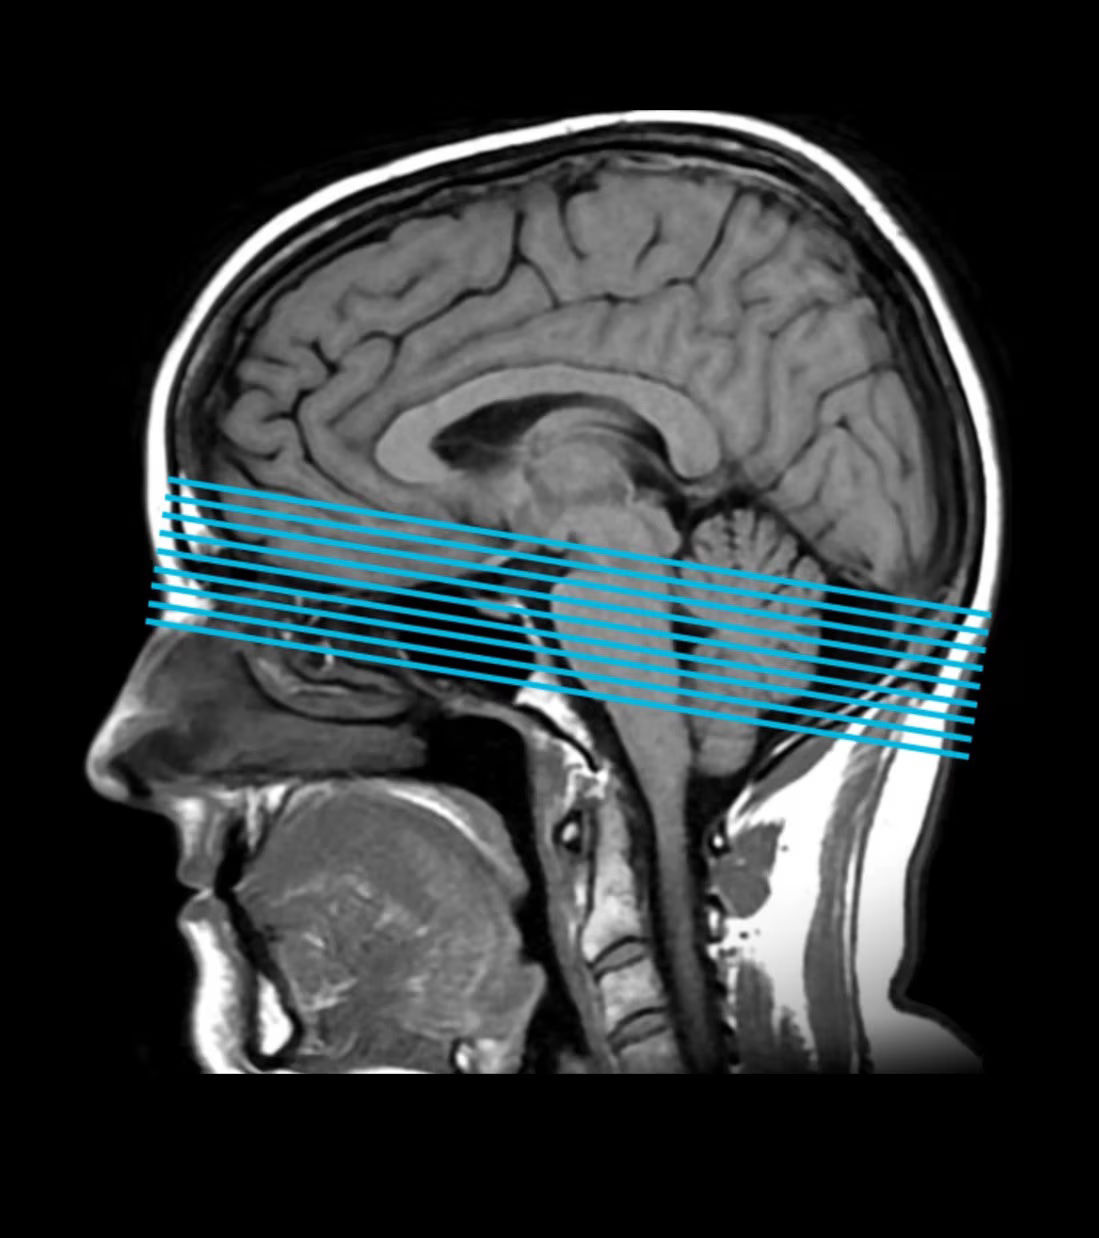

Automatically detect anatomy and prescribe slices based on the anatomical reference and orientation defined for the most commonly requested exams

Deliver consistent and quantifiable results regardless of pathology, patient position, time between scans and technologist variability

Save time by automating slice placements and avoid repeat scans

Everything that it says it can find, it finds it with amazing accuracy. For example, if I tell AIR x™ that I want an oblique sagittal of the left optic nerve, it puts a slice right down the center of that left optic nerve immediately. It can save me some eye strain, save time from tweaking parameters, and get me going a little bit faster. AIR x™ is right... every single time.